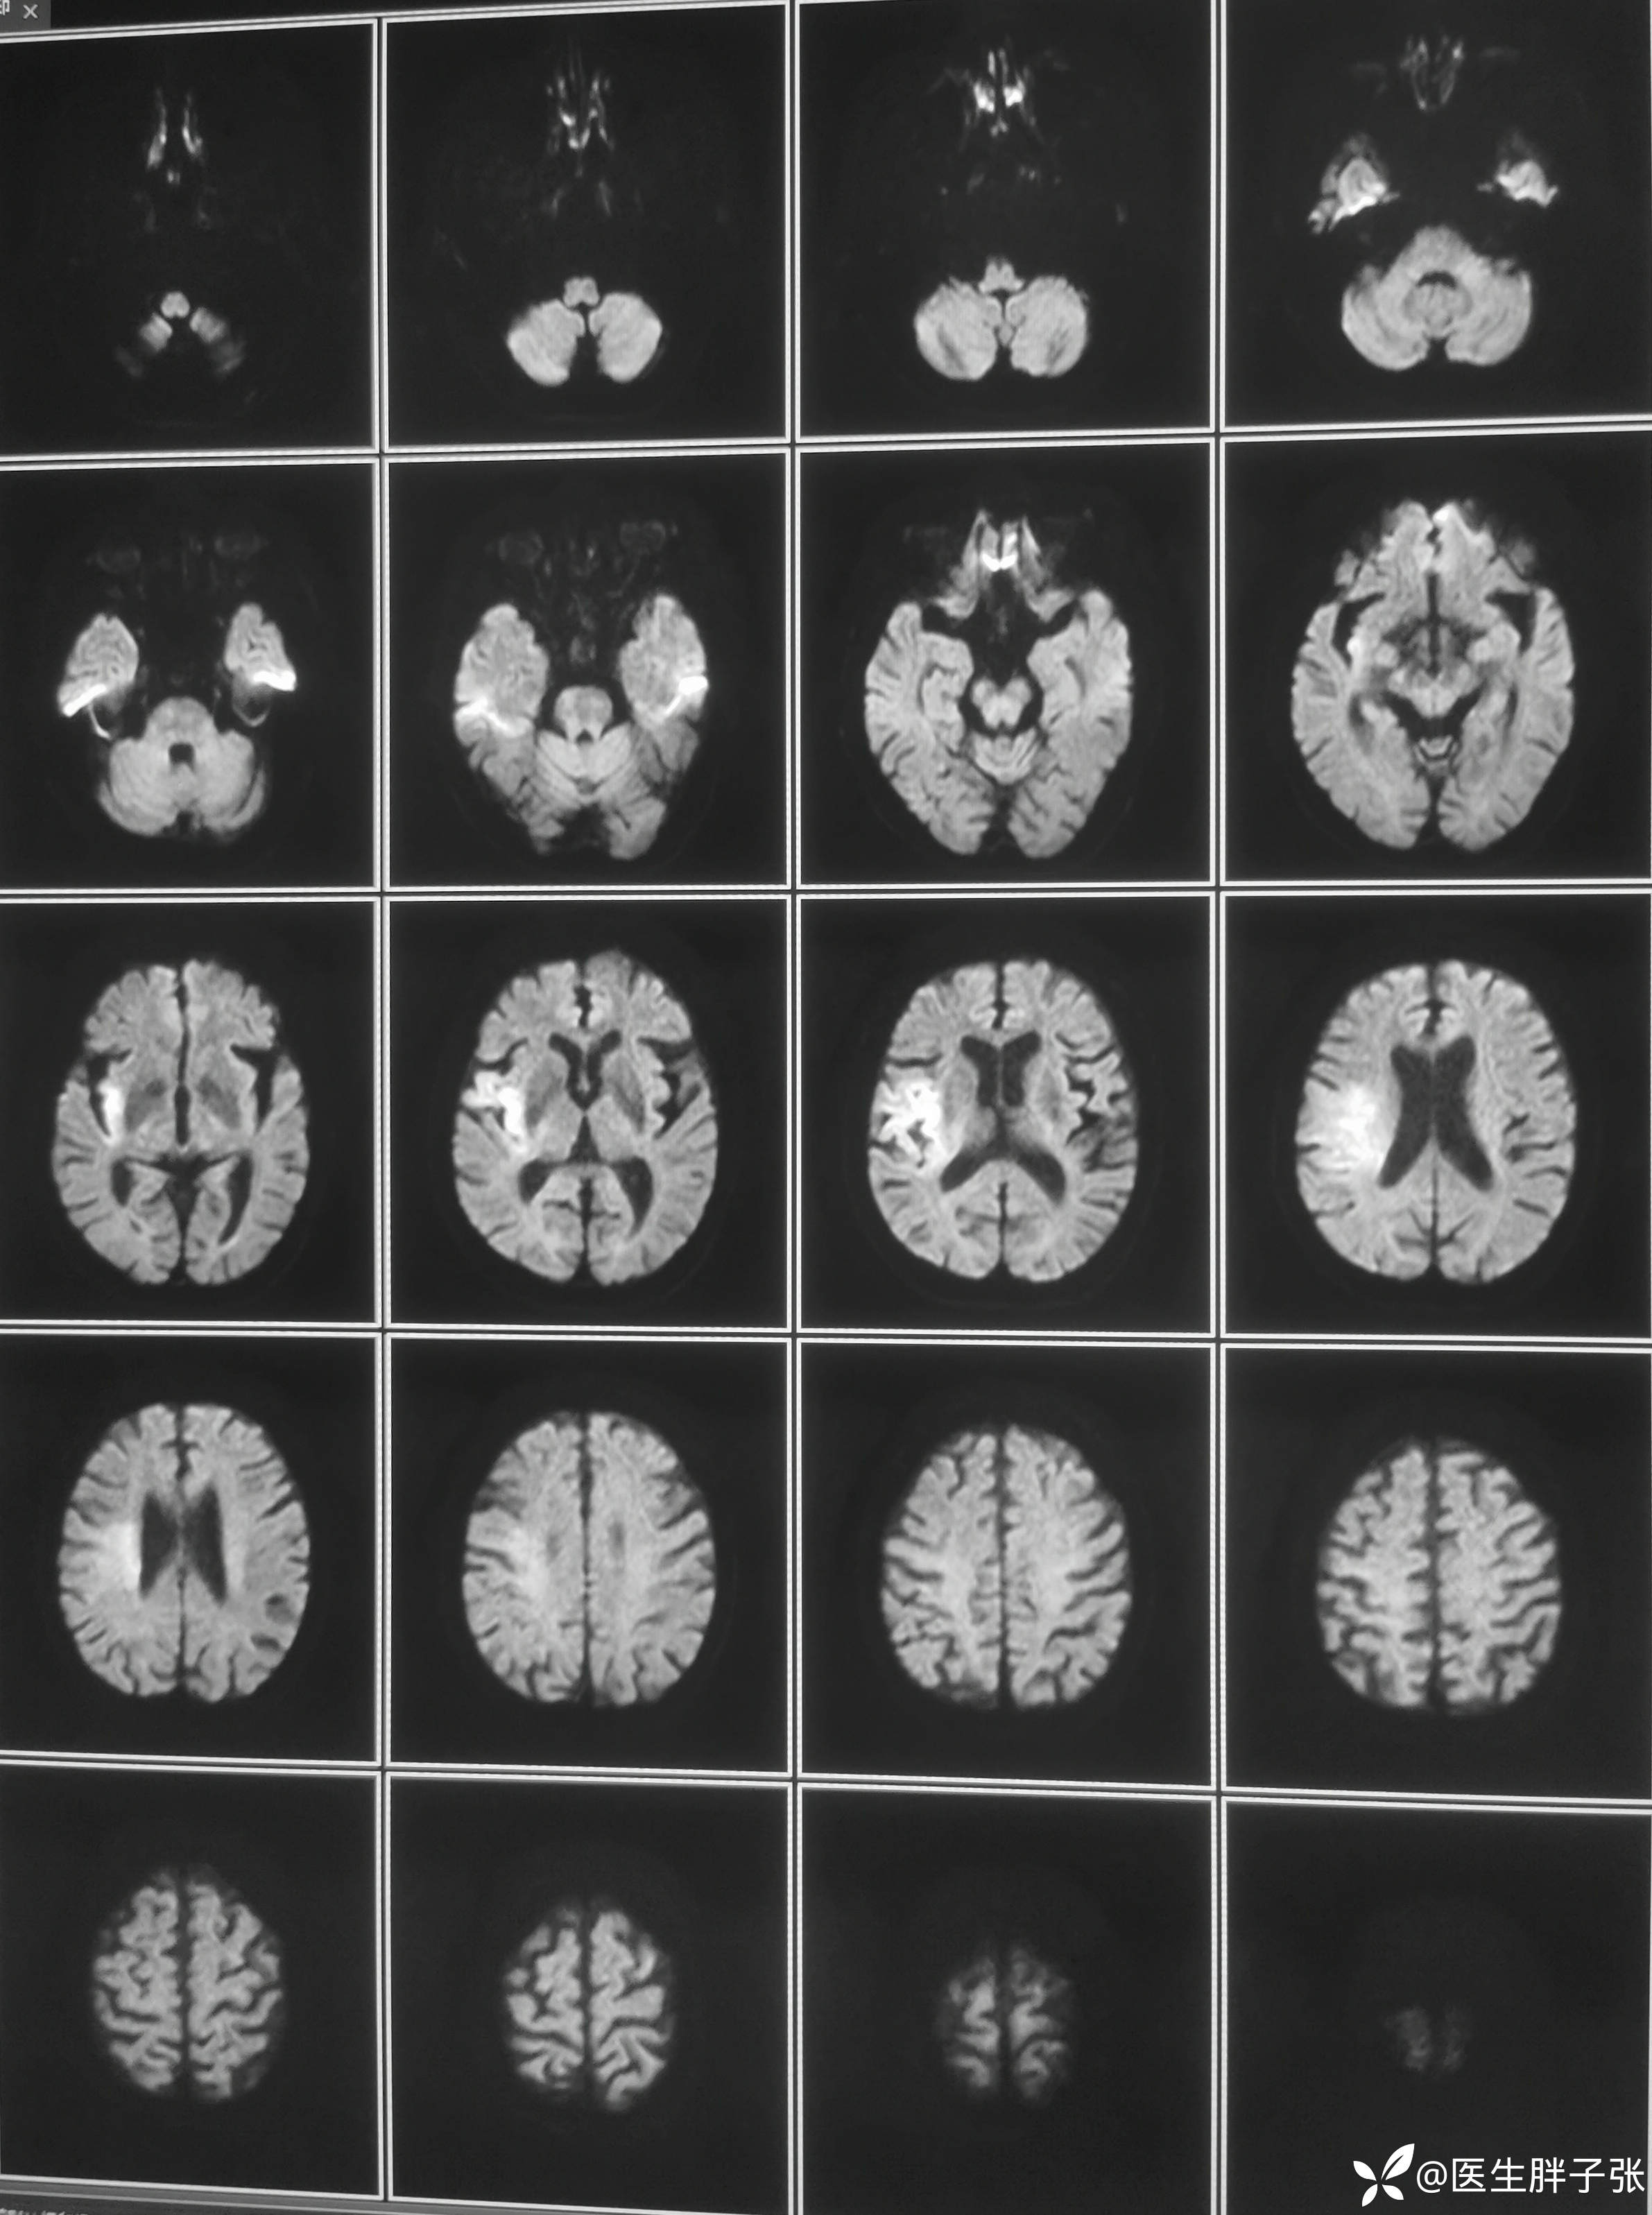

颅脑MR:右侧颞叶新近梗死灶;老年性脑改变;右侧大脑中动脉部分M2段及以远未见显示,建议头颈部CTA检查。

患者为醒后卒中患者,幸运的是恰好晨起交班的时候来院,恰好能查核磁,核磁提示存在DWI-FLAIR错配